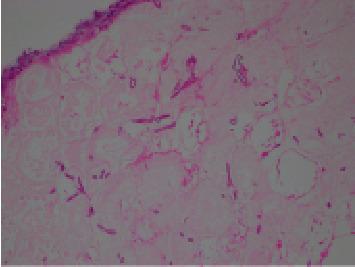

免疫功能正常儿童轻微皮肤创伤后发生的皮肤毛霉病

Cutaneous Mucormycosis in an Immunocompetent Child following a Minor Skin Trauma.

Cutaneous mucormycosis is a rare infection by the class of fungi, which carries significant morbidity and mortality. While typically associated in patients with underlying immunocompromise (especially in the current era of COVID-19), it may also be seen in immunocompetent patients. We report a case of a healthy 4-year-old girl with acute right leg cellulitis and abscess formation, who required surgical debridement following poor response to antibiotic therapy and initial incision and drainage. Tissue histopathology returned cutaneous zygomycosis despite negative tissue cultures. At four-week follow-up, her wound was healed well. Clinicians should maintain a high degree of clinical suspicion for cutaneous mucormycosis given its potential for rapidly progressive and disseminated disease. Currently, the mainstay of diagnostic investigations is tissue histopathology, with a growing role for tissue fungal PCR. Treatment involves multidisciplinary management between surgeons and Infectious Diseases team to guide the role for surgical debridement and antifungal therapy.

摘要